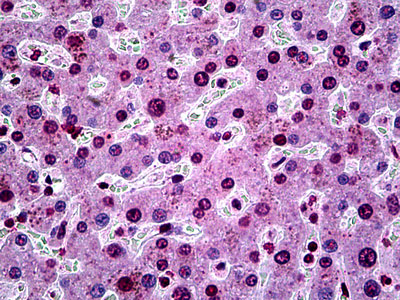

Images |

Anti-SGK1 antibody IHC of human liver. |